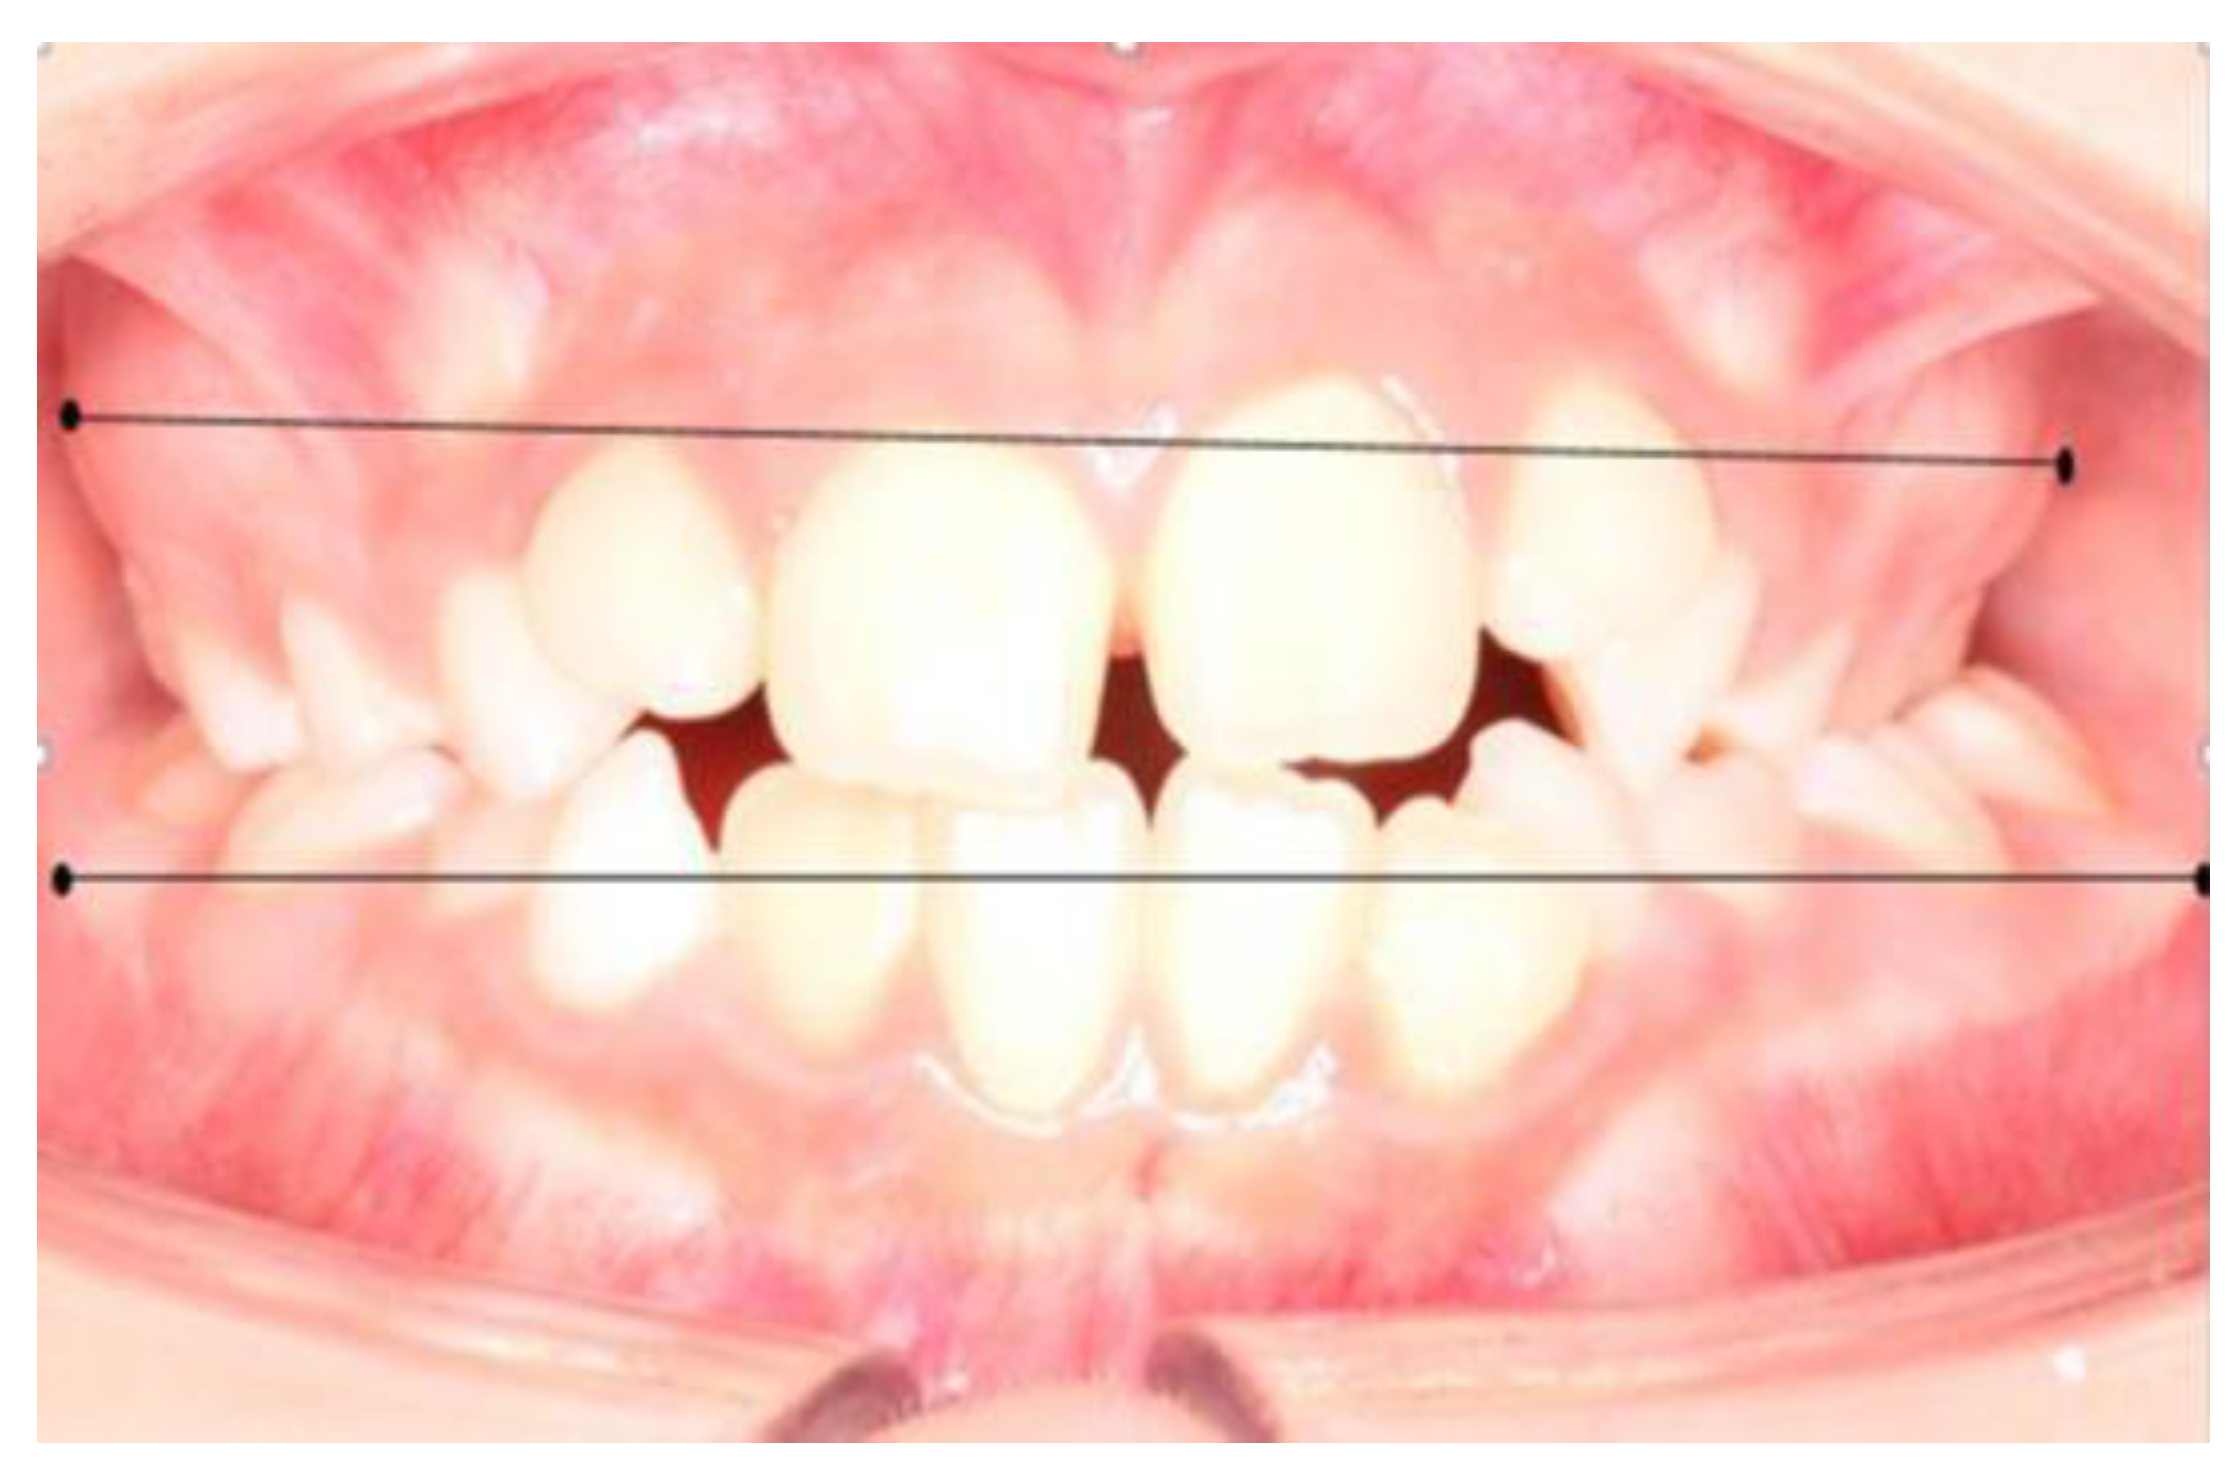

The maximum bone contour lines (mucogingival line) superior and inferior were located on the intraoral photograph, marking the most prominent point at the level of the first permanent molars, defining it as the Wala Ridge point (Wr). From the WR point of the first upper right molar to the WR point of the first upper left molar, a line called the maxillary line (Lmx) was drawn, proceeding in the same way in the lower arch, the mandibular line (Lmd). This way, two linear measurements were obtained (Figure 3) which, when subtracted, resulted in the maxillomandibular difference. For the measurement of the upper wala ridge and lower wala ridge distances, the Meazure® measurement program was used.

Figure 3. Measurement of maxillary and mandibular width from the location of the Wala Ridge points at the level of the first permanent molar. Figure obtained by Dr. Ramon Herrero R.